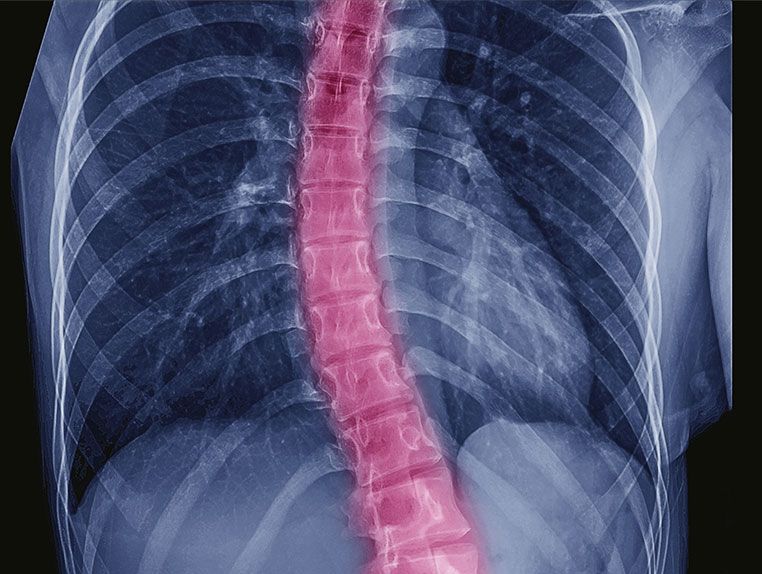

Ihr Wirbelsäulenspezialist in Wien

Minimalinvasive und konservative Behandlungsansätze für Ihre Gesundheit

Wenn Rückenschmerzen oder neurologische Beschwerden Ihre Lebensqualität einschränken, sind Sie bei uns in den besten Händen. Als erfahrene Spezialisten für die Behandlung von Wirbelsäulenerkrankungen bieten wir Ihnen modernste Therapieverfahren, die individuell auf Ihre Bedürfnisse abgestimmt sind.